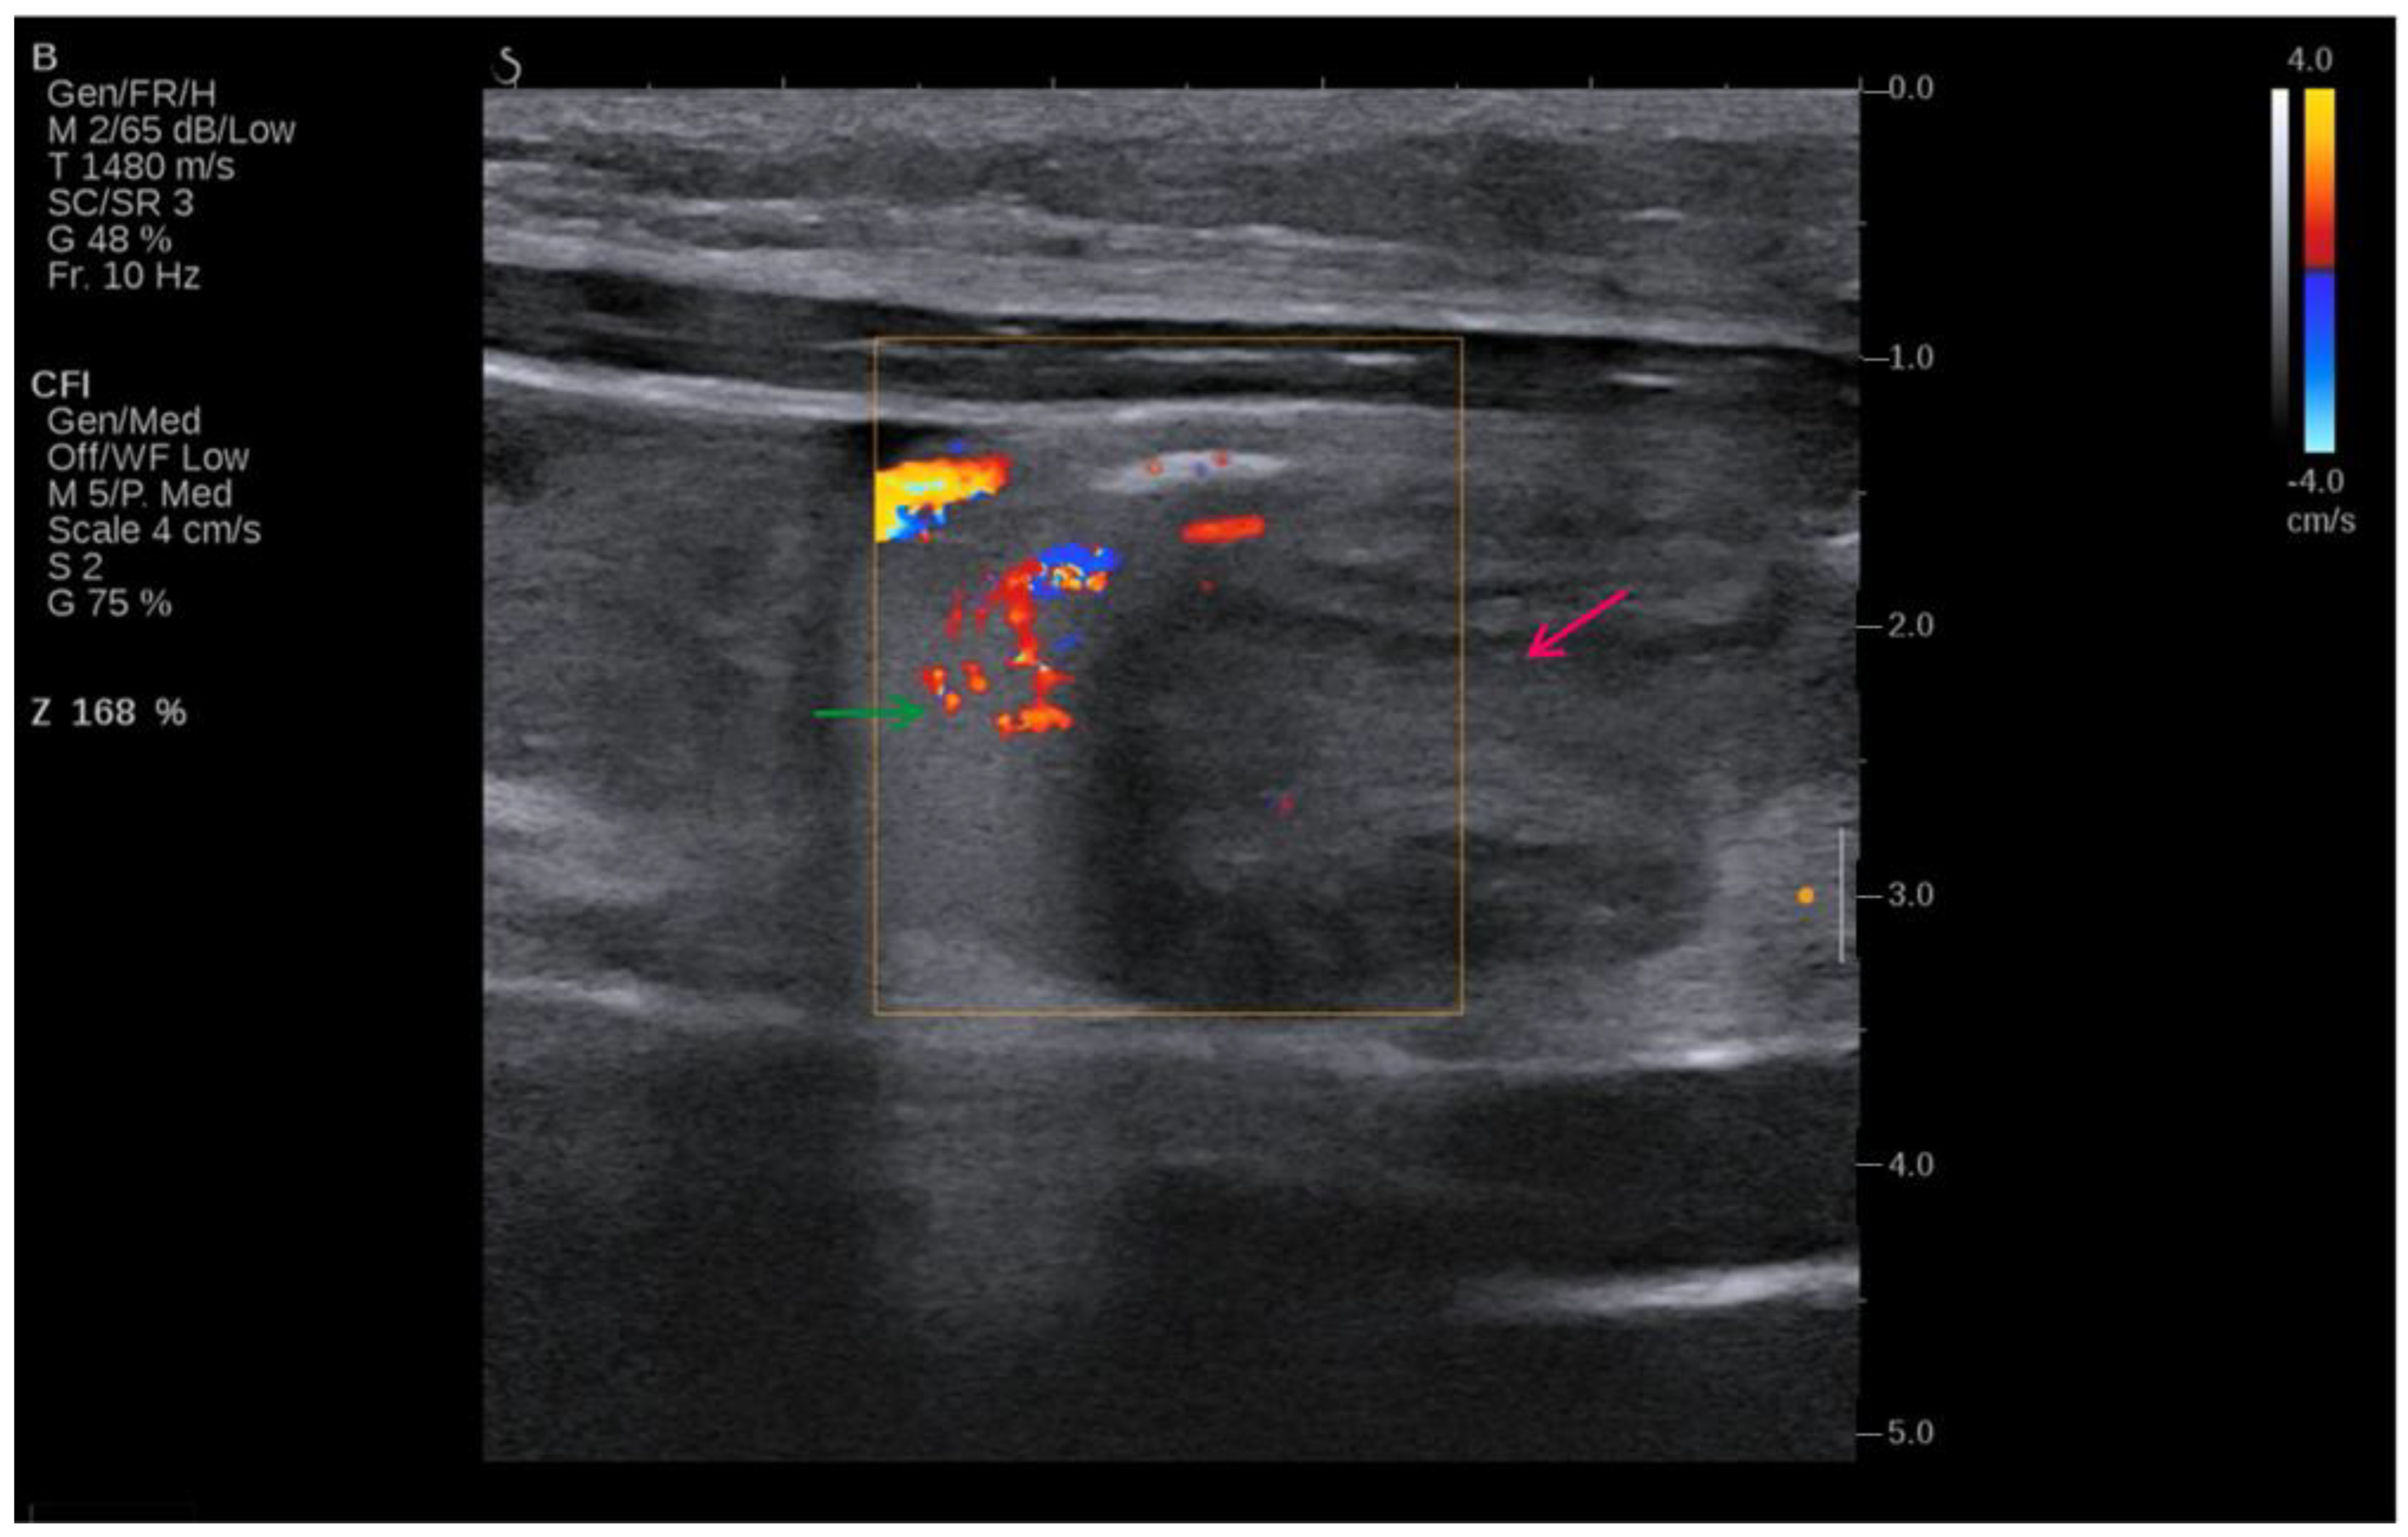

Figure 2 shows that initial imaging with ultrasound was used due to its non-invasive nature and ability to provide real-time imaging, allowing for the evaluation of soft tissue structures and the detection of fluid collections.

Figure 2.

Ultrasound image of the volvulus—intestine twists around itself and its mesentery (red arrow), “whirlpool sign” (green arrow).

This ultrasound image of the patient shown in Figure 2 indicates volvulus, and it can be seen where the intestine twists around itself and its mesentery (red arrow). The image is enhanced with Doppler colour flow mapping, showing swirling blood flow patterns, which is characteristic of the “whirlpool sign” (green arrow). The Doppler settings, as noted on the left side of the image, indicate adjustments made for optimal visualization of the blood flow, capturing the dynamic nature of the twisting vessels. The colour flow imaging reveals areas of both high and low velocities, portrayed in shades of red and blue, corresponding to blood flow towards and away from the transducer. This sign is critical in diagnosing volvulus, as it directly visualizes the torsion of the bowel and its mesenteric vessels, proving sufficient information for an emergency surgical procedure. The surrounding tissue appears hypoechoic, consistent with fluid accumulation due to obstruction.

4.3. Ultrasound Findings of Intestinal Volvulus Due to Extragenital Endometriosis

Typical ultrasound features of intestinal volvulus include the “whirlpool sign”, which represents the twisted bowel loops and the mesentery around the point of torsion. This feature was first described by Vijayaraghavan in 2004 [44], who noted that this is a critical ultrasound finding representing the torsion of anatomical structures, such as the intestines or the adnexa, around their supporting vasculature. Higashide et al. [45] also added that this sign is characterized by the presence of a spiral or whirlpool-like appearance of the twisted bowel loops and the mesentery, or the twisted adnexa, visible on Doppler ultrasound as swirling of the vessels [45].

Rousslang et al. [46] has noted that there might be reduced or absent peristalsis in the affected segment, and increased echogenicity can be seen in the mesentery due to congestion and edema. The presence of free fluid in the abdominal cavity can also be noted, which indicates a more advanced or complicated volvulus [46]. Barra et al. [47] have identified that in the context of endometriosis, these ultrasound findings can be further complicated by the presence of endometriotic lesions, which might appear as hypoechoic or heterogeneous masses within the bowel wall or attached to the surrounding structures. Other studies have also shown that transvaginal and transabdominal ultrasounds can help in identifying these lesions, especially when combined with a detailed patient history and clinical examination. For instance, Hudelist et al. [48] have highlighted the significance of transvaginal ultrasonography in the diagnosis of deep infiltrating endometriosis that affects the colon. In such cases, the lesions are typically observed as irregular nodules or a thickening of the gut wall.

Bazot et al. [49] have conducted research into the use of transvaginal sonography in diagnosing intestinal endometriosis. Their results indicated that transvaginal ultrasound had a sensitivity of 91% and a specificity of 98% in accurately detecting rectosigmoid endometriosis when compared to the findings from surgery. Similarly, Guerriero et al. [50] performed a comprehensive evaluation and statistical analysis that verified the diagnostic accuracy of transvaginal ultrasonography in detecting intestinal endometriosis. They also reported combined sensitivity and specificity values of 91% and 98%, respectively.

The combination of these findings—the whirlpool sign, dilated bowel loops, and the presence of endometriotic lesions—can provide strong indicators for diagnosing intestinal volvulus due to endometriosis. However, further imaging with CT or MRI is often required for a more comprehensive assessment and to plan the appropriate surgical intervention.